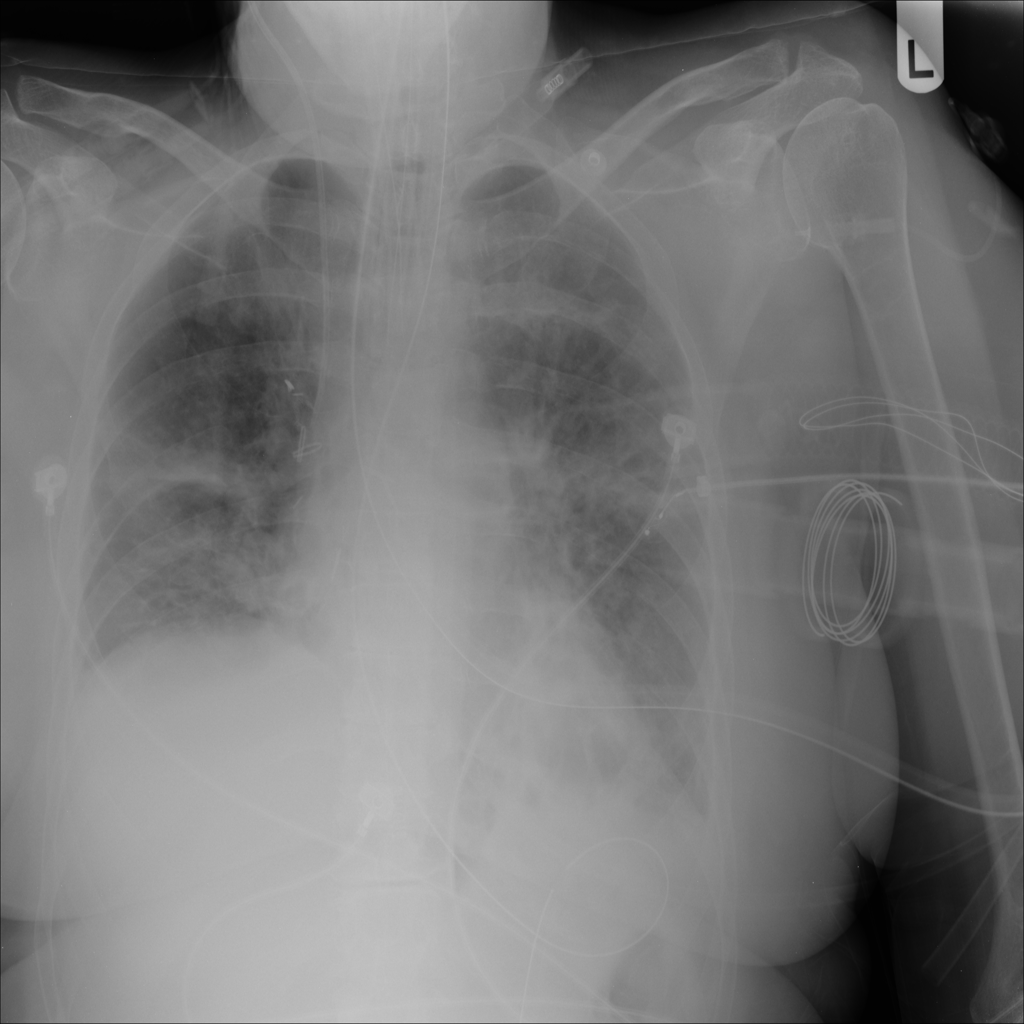

PAT-86C8 · IMG-000Effusion

PAT-86C8 · IMG-000

PA